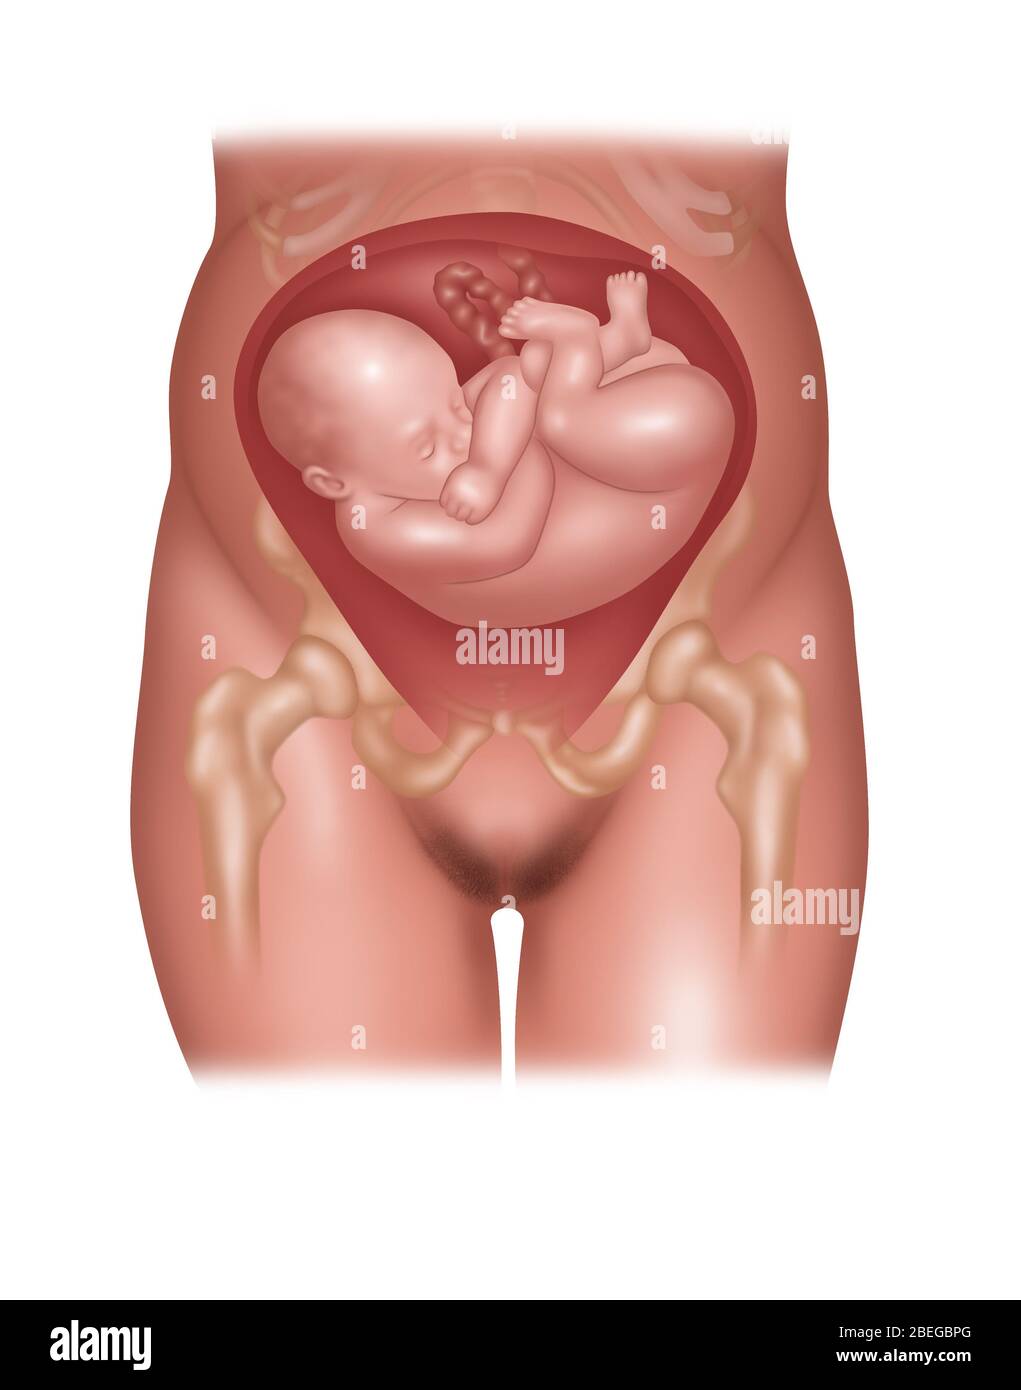

Fetus Positions in Uterus, Illustration Stock Photohttps://www.alamy.com/image-license-details/?v=1https://www.alamy.com/fetus-positions-in-uterus-illustration-image353173031.html

Fetus Positions in Uterus, Illustration Stock Photohttps://www.alamy.com/image-license-details/?v=1https://www.alamy.com/fetus-positions-in-uterus-illustration-image353173031.htmlRF2BEGBPF–Fetus Positions in Uterus, Illustration

Fetus Positions in Uterus, Illustration Stock Photohttps://www.alamy.com/image-license-details/?v=1https://www.alamy.com/fetus-positions-in-uterus-illustration-image353173074.html

Fetus Positions in Uterus, Illustration Stock Photohttps://www.alamy.com/image-license-details/?v=1https://www.alamy.com/fetus-positions-in-uterus-illustration-image353173074.htmlRF2BEGBT2–Fetus Positions in Uterus, Illustration

Fetus in Shoulder Position, Illustration Stock Photohttps://www.alamy.com/image-license-details/?v=1https://www.alamy.com/fetus-in-shoulder-position-illustration-image353173032.html

Fetus in Shoulder Position, Illustration Stock Photohttps://www.alamy.com/image-license-details/?v=1https://www.alamy.com/fetus-in-shoulder-position-illustration-image353173032.htmlRF2BEGBPG–Fetus in Shoulder Position, Illustration